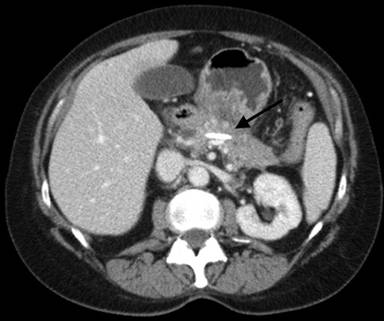

Unfortunately, our patient went on to have quite a complicated course after the index admission. She was readmitted several times with recurrent symptoms of abdominal pain and vomiting over the next several months. She underwent drainage of a peripancreatic fluid collection that was felt to be an abscess and eventually developed necrosis of the mid portion of the pancreas, which resulted in ductal disruption. In addition, she developed thrombosis of the splenic vein. She underwent ERCP and stent placement across the disrupted duct (Figure 4) and was managed over this time period with total parenteral nutrition and bowel rest.

Figure 4. Coronal CT image demonstrating pancreatic ductal stent (black arrow). |